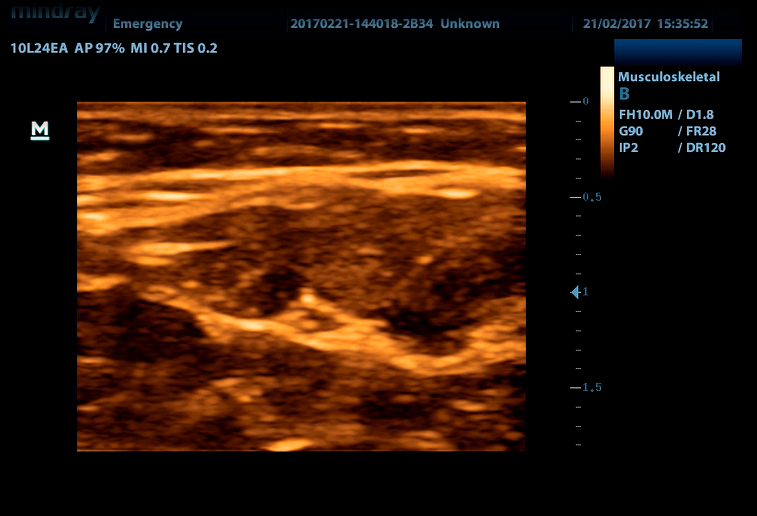

Линейный датчик высокочастотный 10L24EA (8.0/10.0/12.0/14.0/Н10.0/Н12.0 МГц, 24 мм)